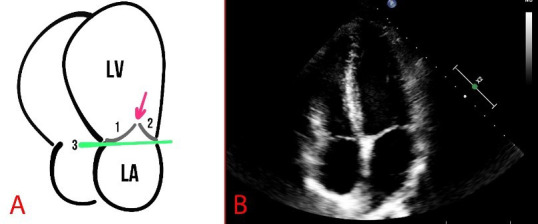

二尖瓣脱垂(MVP),也被称为二尖瓣软陷综合征、收缩期咔嗒声杂音综合征、二尖瓣小叶翻滚,是一种发育异常,在收缩期,当一个或两个异常的瓣小叶移位到二尖瓣环以下的左心房时引起的。在普通人群中2-3%的患者中观察到MVP,是发达国家二尖瓣反流(MR)的主要原因。总的来说,MVP被认为是良性的发育异常;然而,有证据表明MVP与心源性猝死有关。因此,关于这一患者群体的最佳管理一直在进行讨论,包括药物治疗和手术干预。本综述旨在提供良性和心律失常MVP (AMVP)的概述,其诊断选择和管理的可能性。

Mitral valve prolapse (MVP), also known as floppy mitral valve syndrome, systolic click-murmur syndrome, and billowing mitral leaflets, is a developmental anomaly caused when one or two abnormal valve leaflets are displaced into the left atrium below the mitral valve annulus during systole. MVP is observed in 2-3% of patients in the general population and is the leading cause of mitral regurgitation (MR) in developed countries. Overall, MVP is considered a benign developmental anomaly; however, evidence suggests that MVP is associated with sudden cardiac death. Thus, there have been ongoing discussions about the optimal management of this patient group, which includes both pharmacological treatment and surgical interventions. This review aimed to provide an overview of the benign and arrhythmic MVP (AMVP), its diagnostic options, and management possibilities.